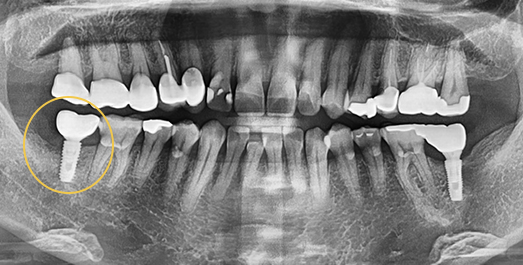

• BEFORE: 2021.02.01

• AFTER: 2021.05.13

Sinus Lift (Sinus Augmentation)

We build up the bone where needed, even when alveolar bone is insufficient.

The maxillary sinus is an air-filled cavity located on either side of the nose, just above the upper alveolar bone, and is lined by a thin membrane. When placing implants in the upper posterior molar region, insufficient alveolar bone in this area may cause the implant to penetrate into the sinus cavity. To prevent this, a surgical procedure called sinus lift (sinus augmentation) is performed — which involves elevating the thin sinus membrane and grafting bone material into the space beneath it.